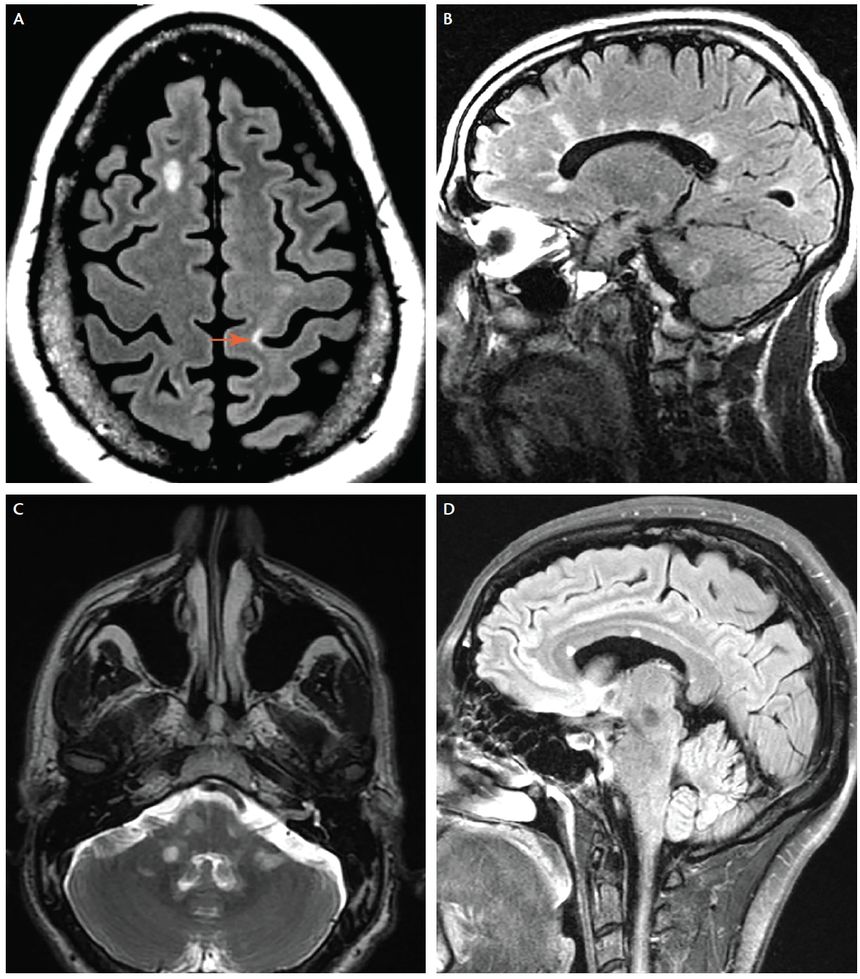

Regardless of origins, autoreactive immune cells target myelin basic protein and degrade myelin. This includes T/B cells, macrophages, and complement. Demyelination increases axonal susceptibility to damage, which is irreversible if severed. Ultimately, the two fundamental underlying processes in disease include focal inflammation, visible as macroscopic plaques, as well as neurodegeneration of the CNS.

Characterised by relapses of neurologic symptoms with stability between, new or recurrent symptoms develop over days to weeks and can present vastly differently for each individual - consider that different neural pathways and areas of the brain may be affected (not everyone will have an MS lesion at the same location in the CNS). This is why the EDSS scale takes into account the differing functional systems. Evaluation is reliant on patient history and physical examination, MRI findings, CSF or blood studies, as well as excluding other causes of the patient's symptoms. The diagnosis of an acute exacerbation/relapse is supported by evidence of historical relapses, confirmed through evidence of one or more lesions.